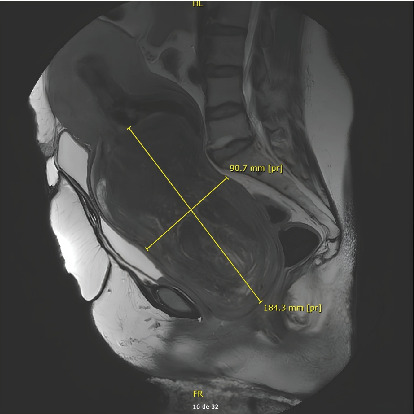

We report the case of a 57-year-old woman who presented to the gynecological emergency department with an enormous 18 cm submucosal leiomyoma pedunculated through the cervix. She was anemic due to bleeding over the past 2 months. The aim of this study was to highlight the challenges of managing such an unusual clinical scenario. We also describe the preoperative and intraoperative methods that can be used to minimize intraoperative blood loss and improve the safety and feasibility of this kind of surgical procedure. In our case, we decided to perform a vaginal myomectomy after a tourniquet on the pedicle to reduce bleeding.